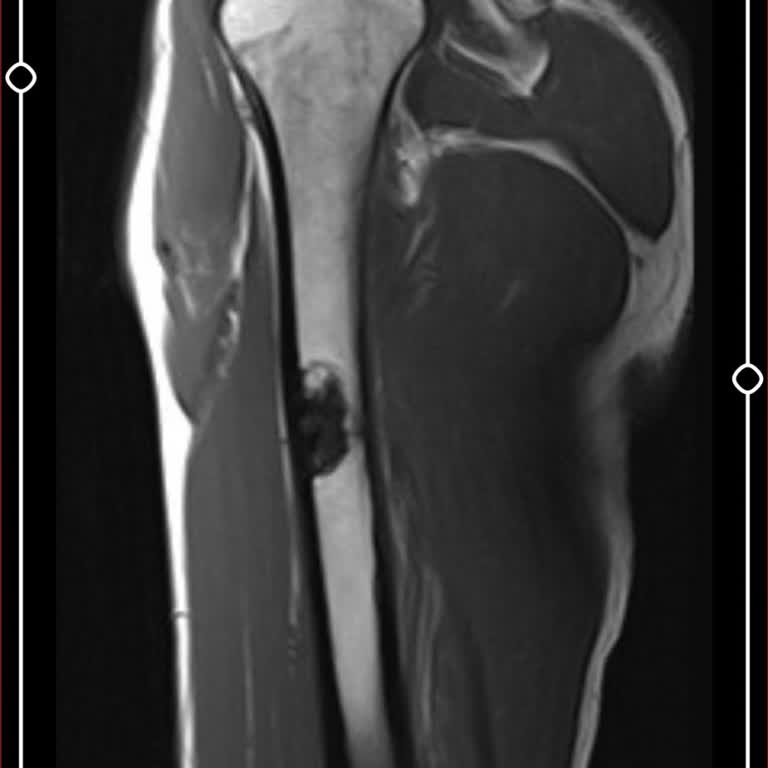

İstanbul Fizik Tedavi ve Rehabilitasyon Eğitim Araştırma Hastanesi’nde 4 Aralık’ta bel MR’ı çektirdim. Bugün 22 Aralık olmasına rağmen hâlâ raporum yazılmadığı için ameliyat sürecim sürekli erteleniyor. 15 Aralık’ta sonucu sormak için hastaneyi telefonla aradığımda, doktorun süresinin bittiği ve kas...